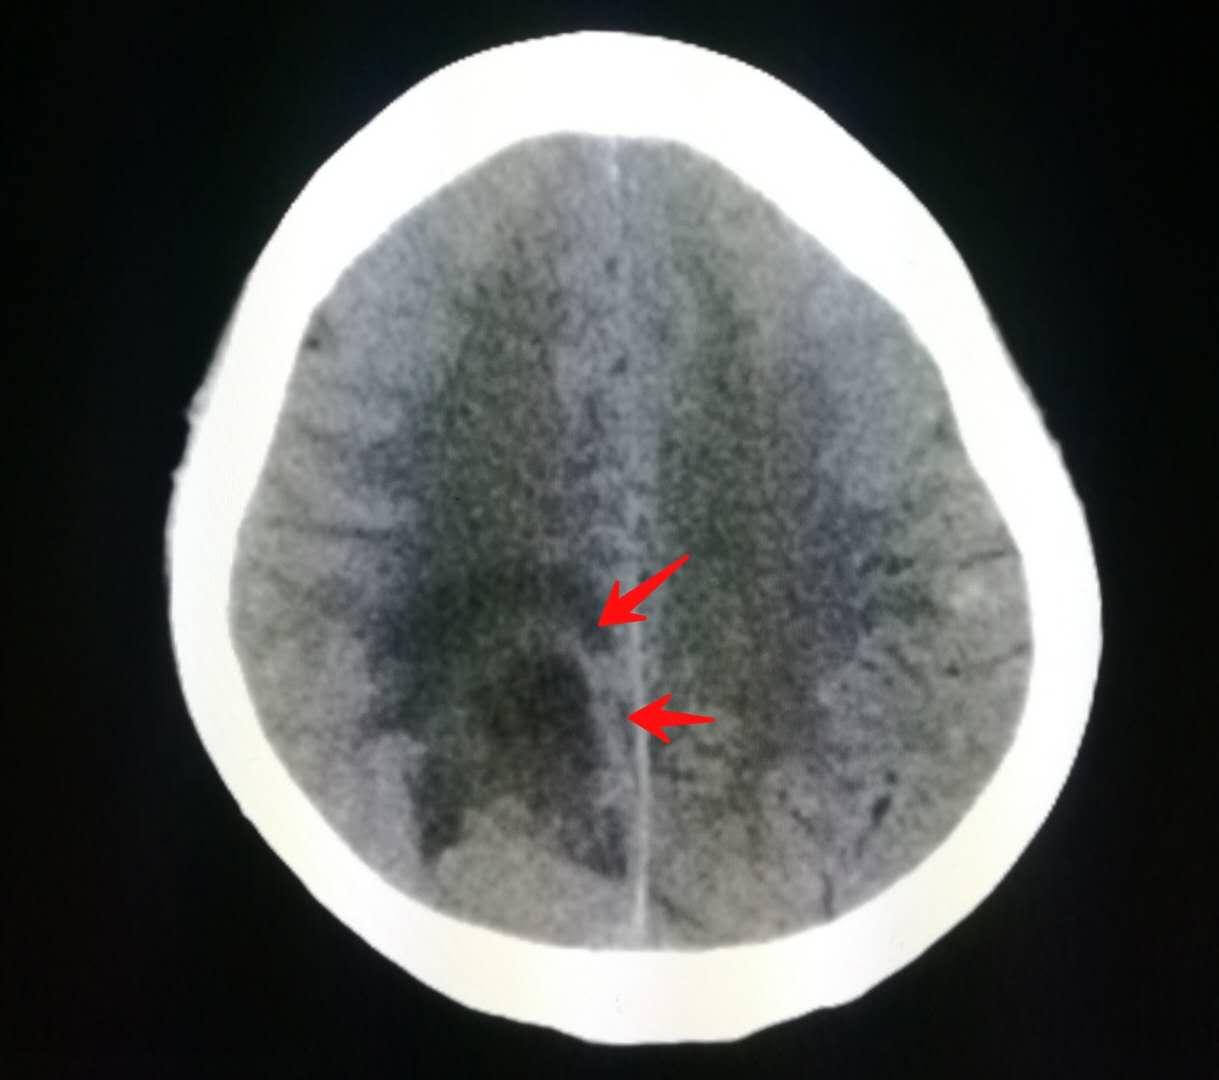

下图就是上周夜班遇到的那位老人,老爷子是一位退休干部,喜欢音乐,在家里弹钢琴的时候突然感觉左侧小指和无名指使不上力,按不动琴键了。

来医院做了脑部核磁共振,发现了脑转移瘤:

紧接着做了胸部CT,证实为右侧肺癌,老人没有任何肺部症状: